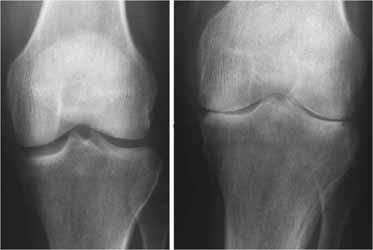

جی پلاس، دکتر خسرو شایان در خصوص عوامل ابتلا به بیماری رماتیسم، اظهار کرد: رماتیسم بیماری است که مربوط به واکنش ایمنی بدن بوده و عوامل ابتلا به آن داخلی هستند. وی با اعلام اینکه برای این بیماری پیشگیری خاصی نداریم، عنوان کرد: به این دلیل که بیماری رماتیسم مربوط به اعضای داخلی بدن و اختلالات آن‌ها است، نمی‌توانیم پیشگیری خاصی را برای آن داشته باشیم. شایان با اشاره به علائم ابتلا به این بیماری، تصریح کرد: زمانی که افراد با تورم و خشکی مفاصل از خواب برمی‌خیزند از علائم ابتلا به بیماری رماتیسم است. معمولا افرادی که رماتیسم مفصلی دارند دچار کم‌خونی شده و بسیار ضعیف هستند. این متخصص ارتوپدی، جراحی استخوان و مفاصل با بیان اینکه افراد در سنین پایین‌ نیز به این بیماری مبتلا می‌شوند، گفت: در بیشتر موارد افراد در سنین نوجوانی و جوانی به رماتیسم مفصلی مبتلا می‌شوند، اما در سنین بالاتر مانند اوایل میانسالی نیز علائم این بیماری خود را نشان می‌دهد. وی به درمان‌های این بیماری اشاره و خاطرنشان کرد: تقویت عضلات مفصلی که به رماتیسم مبتلا شده، جلوگیری از وارد کردن فشار، استفاده از داروهای خاص و ... پیشرفت این بیماری را کندتر می‌کند. شایان ادامه داد: بیماری رماتیسم با آزمایش‌های رماتیسمی و رادیوگرافی مشخص می‌شود. منبع: ایسنا